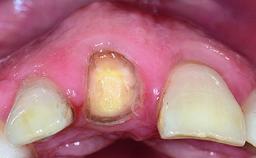

A 32-year-old female Caucasian patient with a compromised maxillary right central incisor was referred to us by a general dentist. Her chief complaints were discomfort and mobility of tooth 11 with unsatisfactory esthetics due to discoloration. The patient reported a previous trauma, some years earlier, as the origin of pathology on the afflicted tooth. Anamnesis was negative for any other dental or periodontal pathology in the remaining dentition. The patient did not take any medication and reported to be a light smoker (5–10 cigs/day). She had high esthetic expectations of her treatment. The extraoral examination revealed a high smile line with full exposure of her maxillary teeth and surrounding soft tissue in the area between the second premolars.

| Provisional Implant-Supported Prosthesis | Prosthodontic margin > 3 mm apical to mucosal margin Prosthodontic margin > 3 mm apical to mucosal margin |

| Interim Prosthesis during Healing | Fixed Fixed |